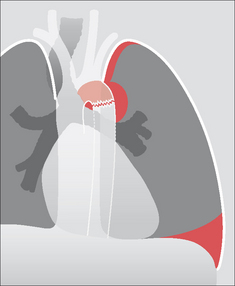

Figure 32.13 Violent trauma. Rupture of a main bronchus. This can cause a pneumomediastinum (arrows), and/or a pneumothorax that fails to absorb following insertion of an intercostal drain, and/or persistent lung or lobar collapse (i.e. persistent lung deflation).